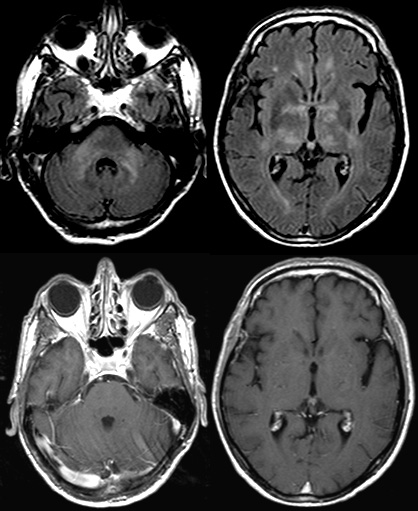

Le grand simulateur

Cas Clinique

Pr Marco Fiorelli Sapienza University of Rome - Rome

Homme de 72 ans

Pas d’antécédents significatifs

Troubles de l’équilibre depuis quelques semaines

Apathie

Perte de poids (12 kg en 2 mois)

Examen neurologique :

Ataxie de la marche

Distrait, peu participant

MMS 27/30

IRM

• Hyperintensité noyaux gris, substance blanche et cervelet

• Pas de rehaussement